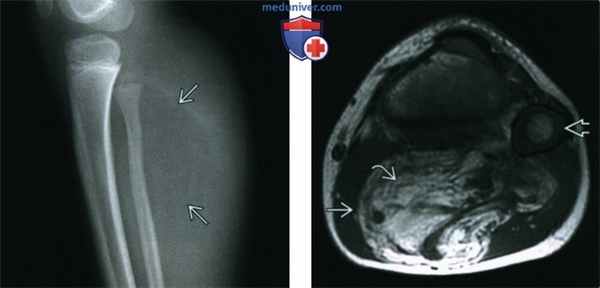

(Слева) Рентгенография в боковой проекции: в средних отделах голени визуализируется умеренно крупная зона просветления. Минимальная деформация контура проксимальных отделов малоберцовой кости, вероятно, обусловлена хроническими изменениями вследствие масс-эффекта. Периостальная реакция или кальцификация мягких тканей отсутствуют.

(Справа) МРТ Т1ВИ, аксиальный срез: в проксимальных отделах голени определяется крупное жировое образование, которое имеет преимущественно жировую интенсивность сигнала, (высокая интенсивность сигнала на Т1ВИ - соответствует сигналу от подкожной жировой клетчатки). Визуализируются выраженные перегородки. Обратите внимание на незрелые зоны роста у этого ребенка младшего возраста.